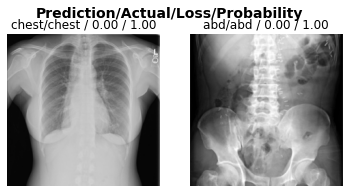

A little more detail on the predictions

Running this cell will provide us with the loss on each image, as well as the model’s predicted probability, which can be thought of as the model’s confidence in its prediction.

Note: If the model is correct and completely confident, the loss should be near “0.00” and the probability will be “1.00”, respectively.

interp = ClassificationInterpretation.from_learner(learn, dl=test_dl)

interp.plot_top_losses(k=2)